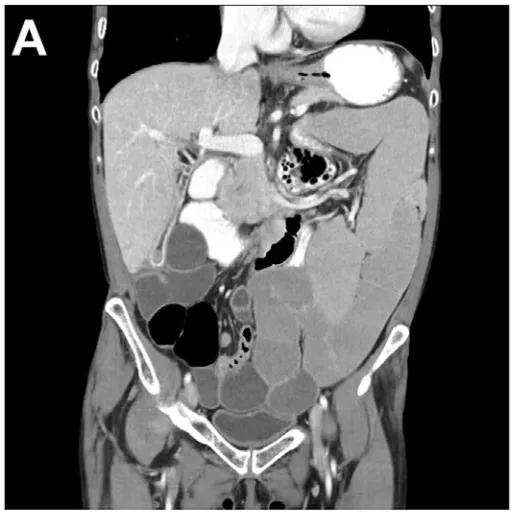

患者女性,54岁,仓库工人,既往健康,因进行性体重下降及肠衰竭由外院转诊至本院,拟行家庭

然而,两年前患者开始出现胃肠道传输缓慢症状,表现为

15个月后,因症状进行性加重并出现疑似中毒性巨结肠的急性临床表现,患者接受了全结肠切除术及末端回肠造口术。但术后症状未缓解,首次出院后4天,患者因持续

考虑到炎症性肠神经节炎的提示,遂行血清抗神经元抗体检测,结果显示抗神经元核抗体(ANNA)-1/Hu和SOX-1抗体阳性。复查氟代脱氧葡萄糖-PET扫描显示右肺下叶存在明显高代谢病灶,伴同侧纵隔淋巴结受累(图E)。